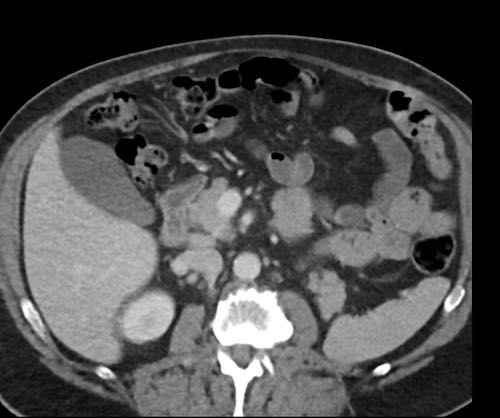

Ca lâm sàng 1

Cuộn qua các lát cắt.

Bạn có thể phát hiện tất cả các tổn thương cấy ghép phúc mạc không?

Bệnh nhân này đã được phẫu thuật và toàn bộ phúc mạc được ghi nhận phủ kín bởi các tổn thương u dạng kê.